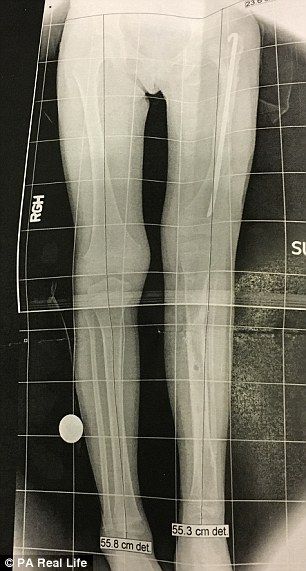

Su hija, Elsie Moravek, nació con una discapacidad rara: su cadera no terminó de formarse correctamente y, por tanto, su pierna y rodilla izquierda solo crecieron a la altura de su otra rodilla. Su pierna izquierda era mucho más corta que la de la derecha.

Así, Elsie consiguió andar con 21 meses, pero lo más duro vendría aún. Después de la cirugía, su madre se comprometió a activar manualmente los tornillos de la prótesis que le colocaron para separar el fémur y la tibia tres veces al día. Por tanto, fracturaron la pierna izquierda de la pequeña Elsie 300 veces a lo largo de cuatro meses, y consiguieron lo que pretendían, que la pierna corta se alargase 10 centímetros.